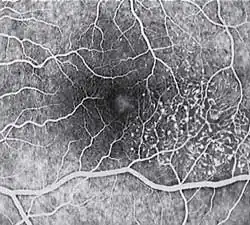

Diagnosis of MacTel type 2 may be aided by the use of advanced imaging techniques such as fluorescein angiography (which may identify an abnormal capillary pattern), fundus autofluorescence, and OCT. These can help to identify the abnormal vessels, pigment plaques, retinal crystals, foveal atrophy and intraretinal cavities associated with this disorder.

Fluorescein angiography (FA) is helpful in identifying the anomalous vasculature, particularly in the early stages of Type 2 disease. Formerly, FA was essential in making a definitive diagnosis. However, the diagnosis can be established with less invasive imaging techniques such as Ocular Coherence Tomography (OCT) and fundus autofluorescence. Some clinicians argue that FA testing may be unnecessary when a diagnosis is apparent via less invasive means.